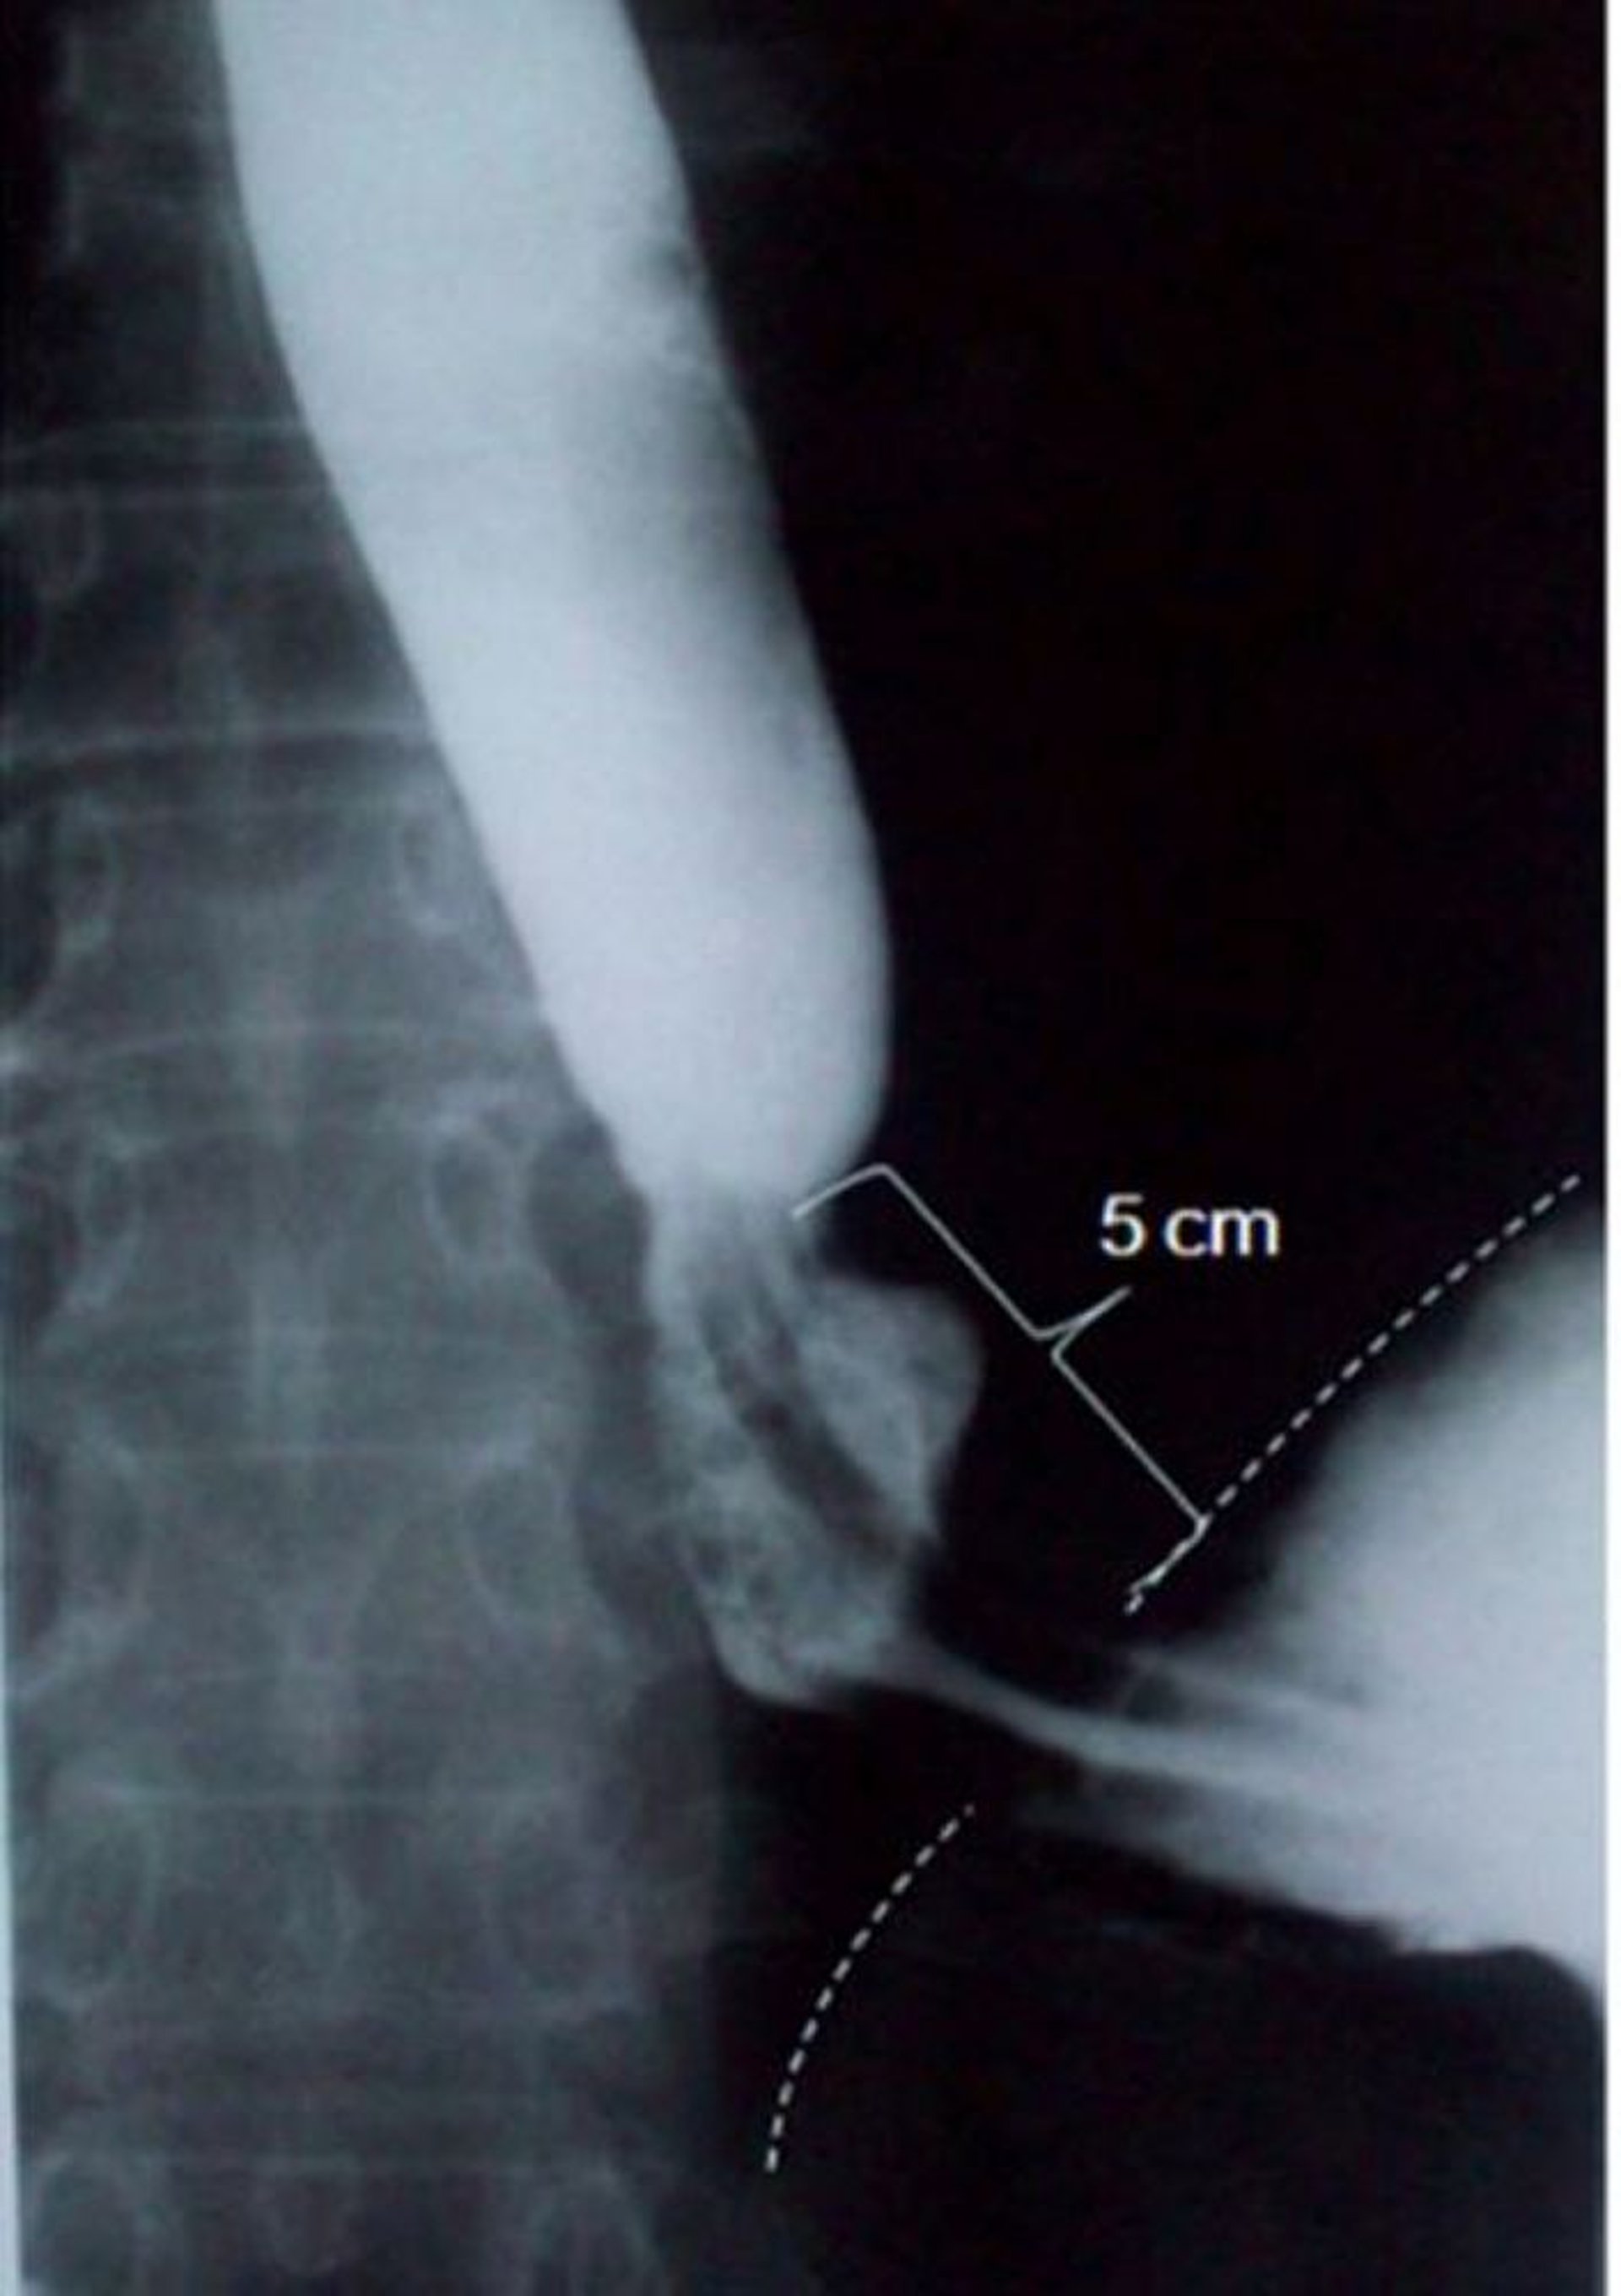

Transit baryté montrant une hernie hiatale par glissement

Cette image montre une hernie hiatale par glissement mesurant 5 cm de longueur axiale (la ligne pointillée indique le bord diaphragmatique).